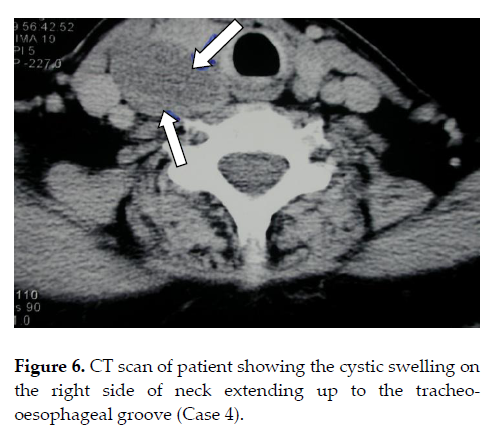

A 52-year-old female presented with history of intermittent dysphagia for solids and liquids since 2 years ago. She had undergone upper GI endoscopy with dilatation on three occasions at different centers. On examination, she had neck fullness on the right with increased local warmth. Barium swallow showed proximal esophagus deviated to the left. A CT scan revealed a 9 X 5 X 3 cm soft tissue collection on the right paratracheal region displacing the thyroid gland anteriorly at C3-T2 level (Figure 6). She underwent excision of the cystic mass (hemorrhagic fluid). The swelling was reported to be a parathyroid cyst on histopathology. Unfortunately she was referred to us only after the histopathology reports. Preoperative calcium and PTH measurements were not available as this pathology was not suspected. Postoperatively her calcium levels were 9mg/dl, albumin 3.4mg/dl, phosphorus 2.6mg/dl and PTH 343 pg/ml.

Figure 6. CT scan of patient showing the cystic swelling on the right side of neck extending upto the tracheo-oesophageal groove (Case 4).